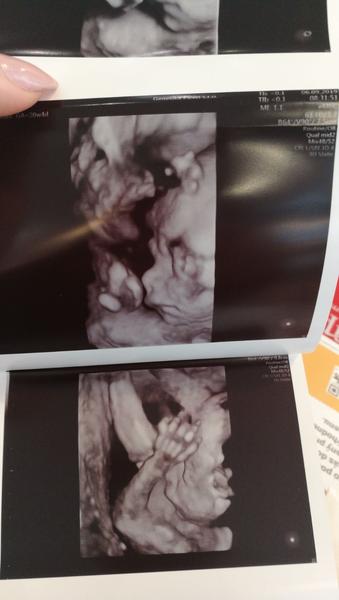

Ahoj holky, tak my máme 2. screening za sebou, byli jsme včera. Vše je v naprostém pořádku a na svém místě, vše funguje tak, jak má, opět potvrzena holčička a bylo super ji opět vidět 🙂 Pán doktor ultrazvuk přepnul na chvíli i na 3D a je to mazec vidět už ty rysy obličejíčku 🙂 Jinak my chodíme do Brna do Prenatalu, platili jsme 1200 Kč a dostali jsme 3D fotečku a nahrávku celého ultrazvuku na CD. Tak pak pisnite váš zážitek 😇

@jennas Tak pak šupní nějakou fotečku z toho 4D, pokud budeš mít, ju? 🙂 My se teda na ty další ultrazvuky (3D a 4D) už objednávat nebudeme. Teď už budeme jen chodit do poradny na gyndu...

@laloogrey @jennas Ahoj holky, tak to oběma gratuluju k pozitivním zprávám, to je moc dobře! 😍 Jsem ráda, že se nám daří, ale zároveń to klepu!!🙂 Já byla v pondělí na kontrole a včera na 3D utz. Na kontrole ok, jsem ve 22+1 a nahoře mám cca 4,2 kg, tak snad je to ok. Nikdo k tormu nic neříkal A vyfasovala jsem žádanku na cukrovku, tak za 14 dní se mám objednat. Tobě @laloogrey držím palce, aby pro tebe ta zvýšená hodnota nic neznamenala a bylo všechno ok!! 😉Jinak já vám taky ukážu naši malou princeznu na fotečce, co jsme dostali🥰